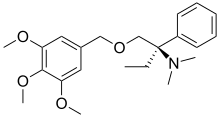

Phenalkoxams

- Dextropropoxyphene (propoxyphene)

- Levopropoxyphene

- Norpropoxyphene

Dextropropoxyphene |